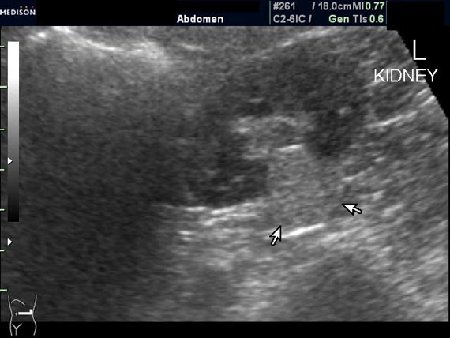

Случайная находка в нижней трети левой почки (не в полюсе, а по задне-медиальной поверхности).

Образование в левой почке

ПО УЗ-семиотике образование соответствует ангиомиолипоме (AML). По правилам в таких случаях необходимо выполнить КТ, доказать преимущественно жировой состав опухоли, затем проводить УЗ-наблюдение.

Согласен. Именно с таким диагнозом (ангиомиолипома) отправил на КТ. Особенностью случая ИМХО является заметный "выход" образования за контур почки (на 2/3 объема).

При ультрасонографии ангиомиолипома выглядит как округлое образование без капсулы с однородной внутренней эхоструктурой и четкими контурами; эхогенность ее чаще всего равна или чуть выше эхогенности перинефральной клетчатки [7]. Значительно реже эхогенность ангиомиолипом может быть равна эхогенности почечной паренхимы; такие опухоли состоят почти полностью из гладкомышечной ткани [8]. Иногда позади ангиомиолипомы может определяться слабая акустическая тень.